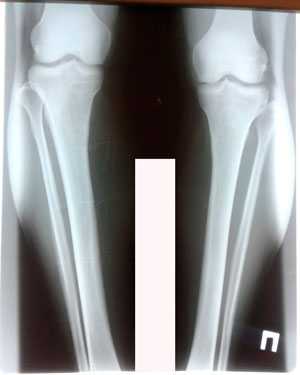

Исходник - 44 года.

Дата операции - 17.03.2020

Дата снятия аппаратов - 17.06.2020

Срок сращения - 90 дней.